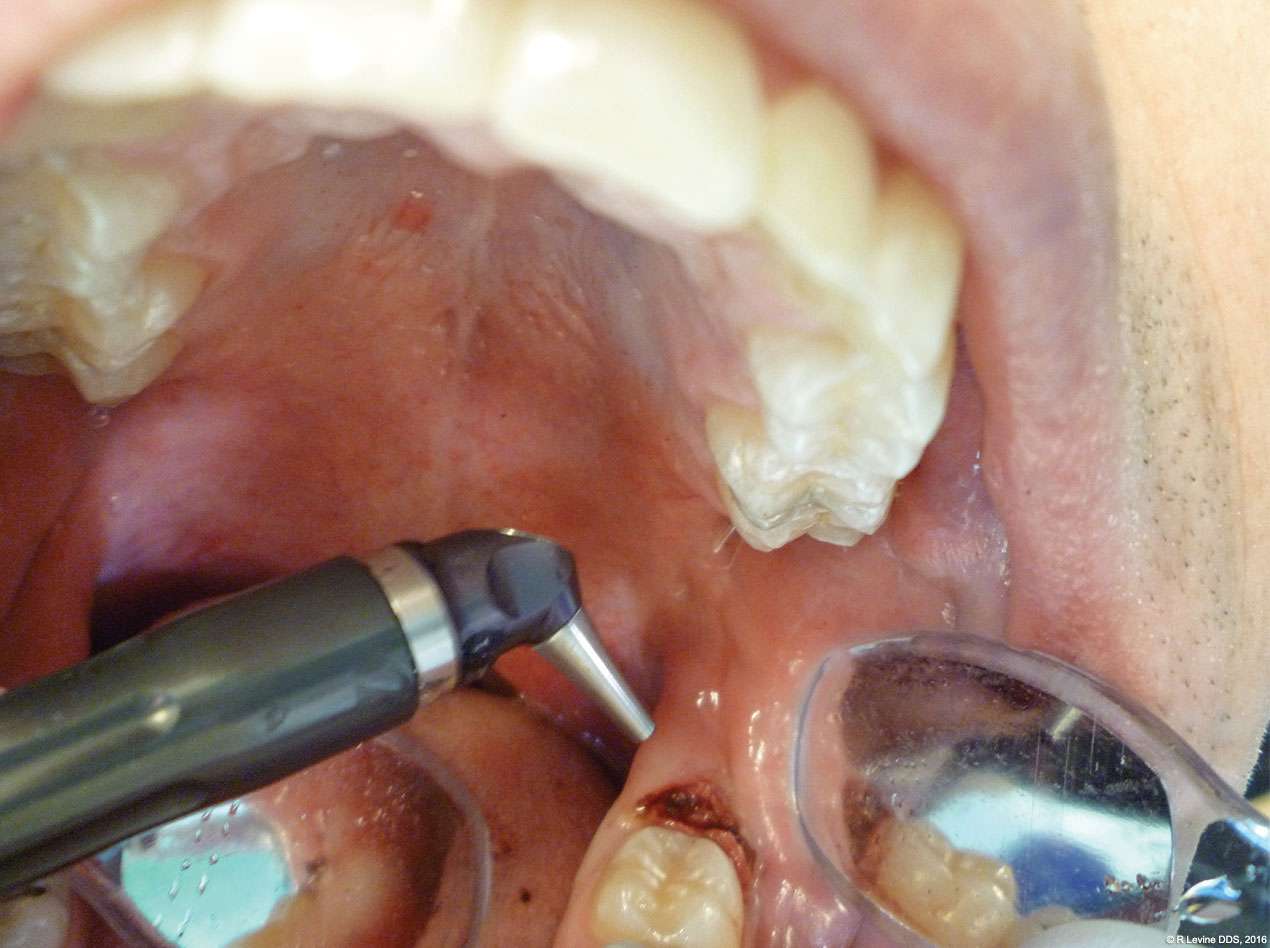

The patient presented with a raised, inflamed, painful operculum distal to the left mandibular second molar (Figure 3). The lesion was red, edematous, and bled easily. A periodontal pocket on the distal of the second molar was > 6 mm deep. There was no evidence of abscess.

- The angled handpiece of the CO2 laser was held perpendicular to the target lesion (Figure 4) and the ablation of the inflamed tissue began (Figure 5). The dental surgeon was careful to avoid contact between the laser beam and the tooth enamel. (Note: In this case, the inflamed tissue was located distally from the involved molar. There was no direct contact of the beam with the tooth, as the surgeon was careful not to hit the enamel. However, if an operculum covers part of the tooth, an adaptive tool (for example, a wax spatula) needs to be inserted between the tissue and the tooth to prevent possible damage. For an inexperienced CO2 laser surgeon, it is important and highly recommended to always shield the tooth during the procedure.[6])